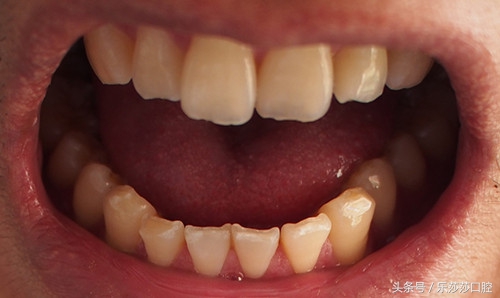

二、严重磨牙导致的牙齿缺损:磨牙一般不会影响到日常生活,但是长期的严重的「磨牙」,会导致牙齿咬合及邻面的「严重缺损」。如果有夜磨牙的情况,可定制夜磨牙垫减少磨损。